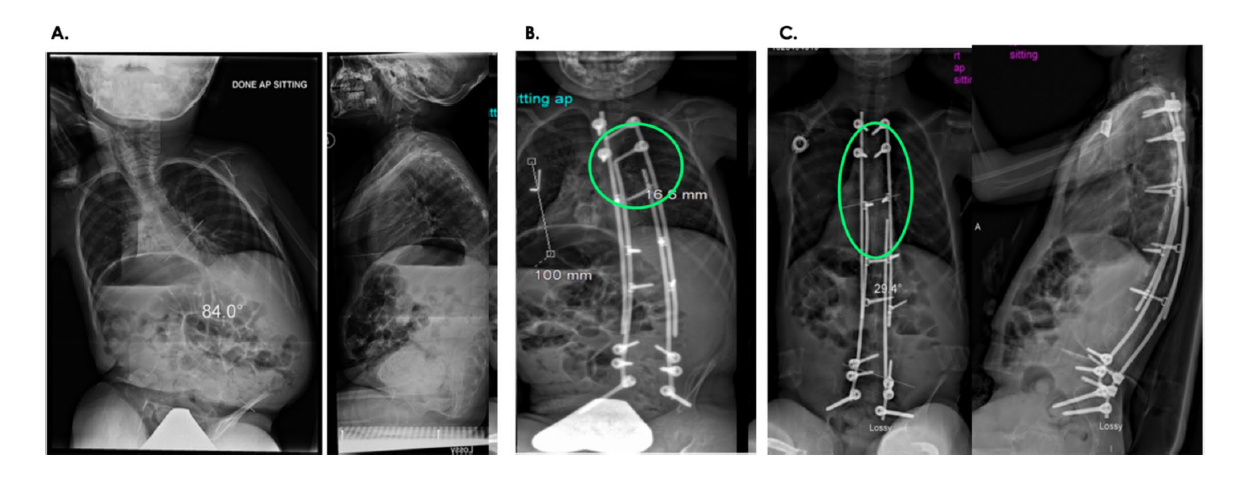

- The MLT group achieved the same curve correction as the controls at 3 years. Initial curve correction was greater in MLT patients, but they experienced more postoperative loss of curve correction.

The MLT technique, which captures the apex of the deformity with gliding anchors via a minimally invasive approach, markedly reduces the need for repeated surgeries in children with EOS. It addresses key limitations of earlier Luque trolley designs and modern growing rod systems, particularly the high rates of implant failure and spontaneous spinal fusion seen in other growth sparing techniques.